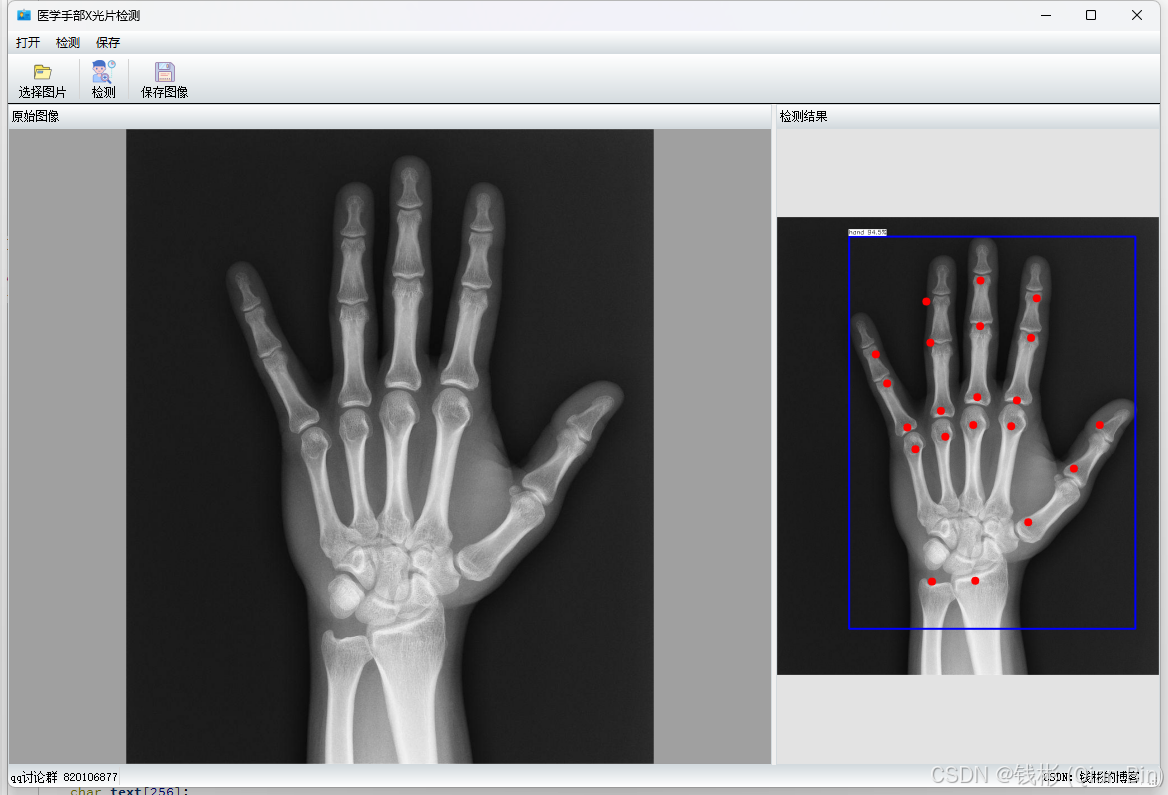

保存所有修改后,运行项目,最终效果如下图所示:

可以看到,这个检测结果跟前面研发阶段的推理是一致的。由于我们的程序全部是采用x86架构编写的,因此可以移植到window7 的32位机器上运行,而64位机器也能兼容运行。这样就满足了在旧设备上完成AI算法研发的任务。